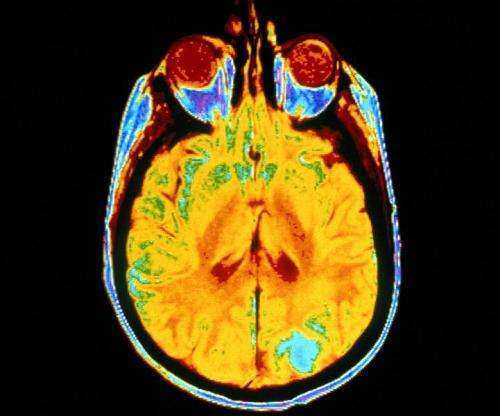

梅奥诊所因利用人工智能通过核磁共振成像手段对某些脑瘤突变进行早期识别的研究成果,而被授予全球影响力大奖(Global Impact Awards)及5万美元的奖金。全球影响力大奖得主布拉德利·埃里克森(Bradley Erickson)博士是梅奥诊所的一名神经放射学家,正在部署通过GPU加速的深度学习技术,以期找到一种能够更快并且更精准的诊断和治疗脑瘤的方法。

这项技术能够帮助医生轻松获取宝贵的遗传信息,帮助医生弄清肿瘤的进化速度、特定药物是否对肿瘤有效、或非手术治疗是否对肿瘤有效。